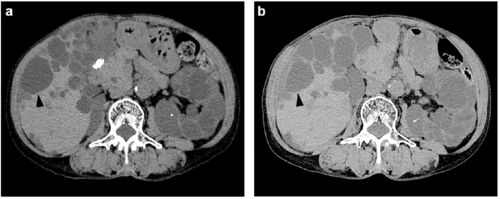

case146:特発性細菌性腹膜炎との鑑別を要する疾患(BMC Gastroenterol. 2021 Jun 24;21(1):267.)

病歴/身体所見/検査所見 ・71歳女性 ・3年前にADPKDによる慢性腎臓病と診断/4年前に右中大脳動脈の未破裂動脈瘤に対してクリッピング術を受けている ・飲酒歴なし、喫煙歴なし ・1か月前に突然右季肋部痛を発症し受診 ◦7カ月前のCTでは認めなかった右肝嚢胞…